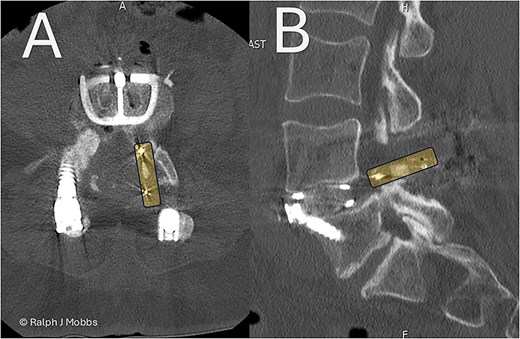

Following standard preoperative preparation, the patient underwent ALIF at L4/5 (Fig. 6). A standard retroperitoneal approach and anterior discectomy were performed [4], with the disc space prepared. Note was made that no graft was within the interbody space, nor any evidence of arthrodesis. A Redmond Ti/PEEK ALIF cage (A-Spine, Taiwan) 14 mm, 12° lordotic cage was inserted with three integral 30 mm screws for segmental fixation (Fig. 1B and C). The ALIF device and interbody space were packed with allograft and autograft material. The construct was confirmed with intraoperative X-ray imaging, and postop CT scan the following day (Fig. 2). Estimated blood loss was minimal (~15 cc), with no intraoperative complications.

Day 1 postop ALIF. The PEEK cage can be seen in the canal and paraspinal regions. (A) Axial sequence. (B) Parasagittal sequence.